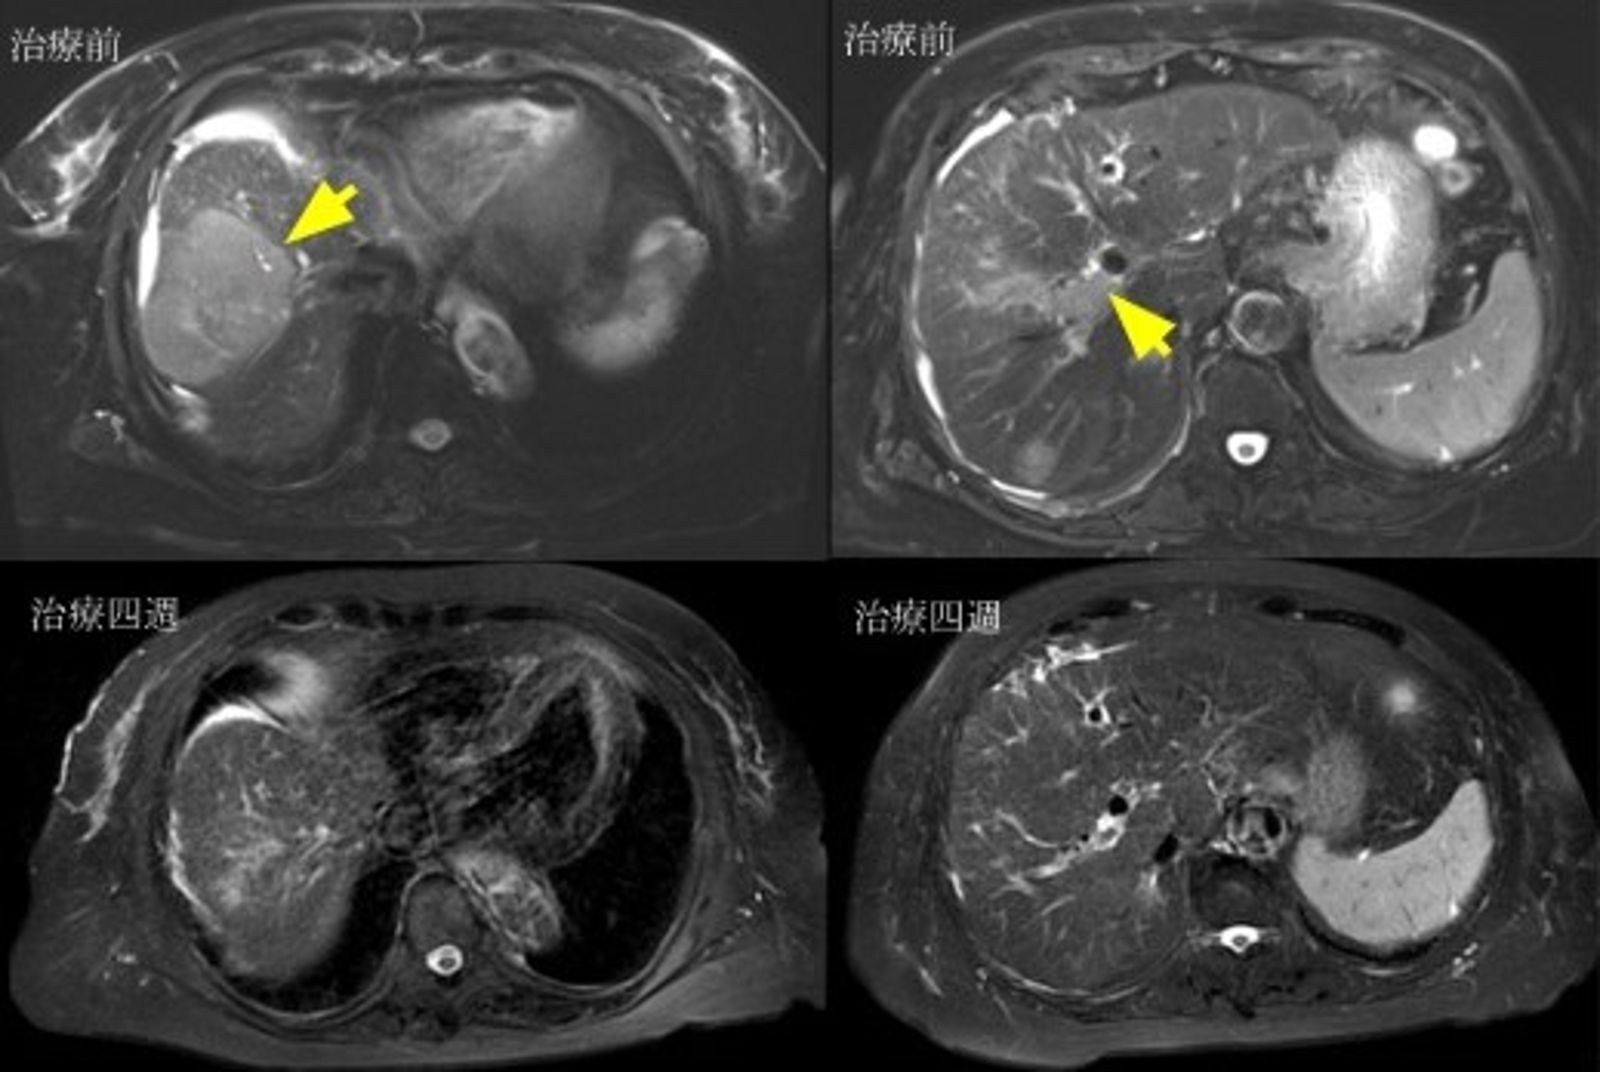

近年,免疫治療的發展為晚期肝癌患者帶來新的希望,尤其是「雙免疫療法」,結合PD-L1與CTLA-4雙重免疫檢查點抑制劑,成為晚期肝癌第一線治療的重要武器。台灣肝癌醫學會理事長暨臺北榮總醫學研究部主任黃怡翔教授表示,根據臨床試驗結果,雙免疫療法在亞洲病人族群中的治療反應率突破3成,且長期追蹤顯示部分患者存活期達4至5年以上。